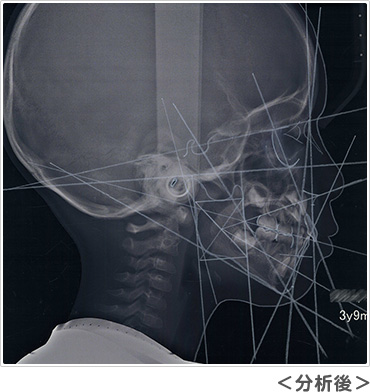

レントゲンは通常大きなレントゲンを2枚撮影します。パノラマレントゲンからは、おもに将来の永久歯の数が足りているか、永久歯の前歯はどのような形で生えてくるか、スペース不足はどのくらいか、などを予測します。セファロレントゲンからは、顔に対してアゴや歯並びがどのくらいの位置にあるのか、将来どのように成長する傾向があるのか、などを基準となる位置の角度を測って計測します。